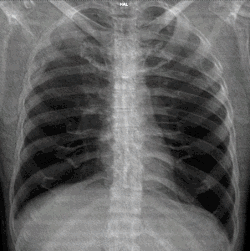

A chest radiograph, chest X-ray (CXR), or chest film is a projection radiograph of the chest used to diagnose conditions affecting the chest, its contents, and nearby structures. Chest radiographs are the most common film taken in medicine.

Different views (also known as projections) of the chest can be obtained by changing the relative orientation of the body and the direction of the x-ray beam. The most common views are posteroanterior, anteroposterior, and lateral. In a posteroanterior (PA) view, the x-ray source is positioned so that the x-ray beam enters through the posterior (back) aspect of the chest and exits out of the anterior (front) aspect, where the beam is detected. To obtain this view, the patient stands facing a flat surface behind which is an x-ray detector. A radiation source is positioned behind the patient at a standard distance (most often 6 feet, 1,8m), and the x-ray beam is fired toward the patient.